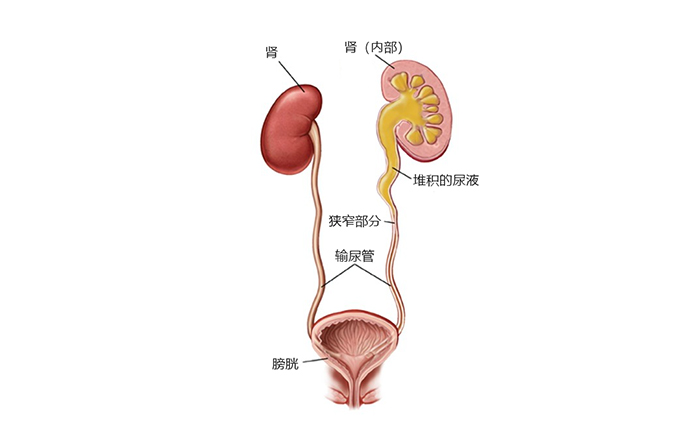

什么是輸尿管狹窄?

輸尿管是一對連接腎臟和膀胱的細長腔道,主要作用是將腎臟中的尿液排入膀胱。當輸尿管出現狹窄時,會導致輸尿管擴張和腎積水,從而出現疼痛,尿道感染,血尿,腎結石等癥狀。可能引發輸尿管狹窄的因素包括腎結石,先天性疾病,醫源性損傷,放射治療,惡性腫瘤等。研究表明,雖然通過腔鏡取石手術后發生輸尿管狹窄的概率只有3.5%,但將近75%的輸尿管狹窄是由醫源性損傷和放射治療所引起的。患者為85歲高齡,術后并發癥的概率相對較高。

來自網絡:輸尿管狹窄導致尿液堆積